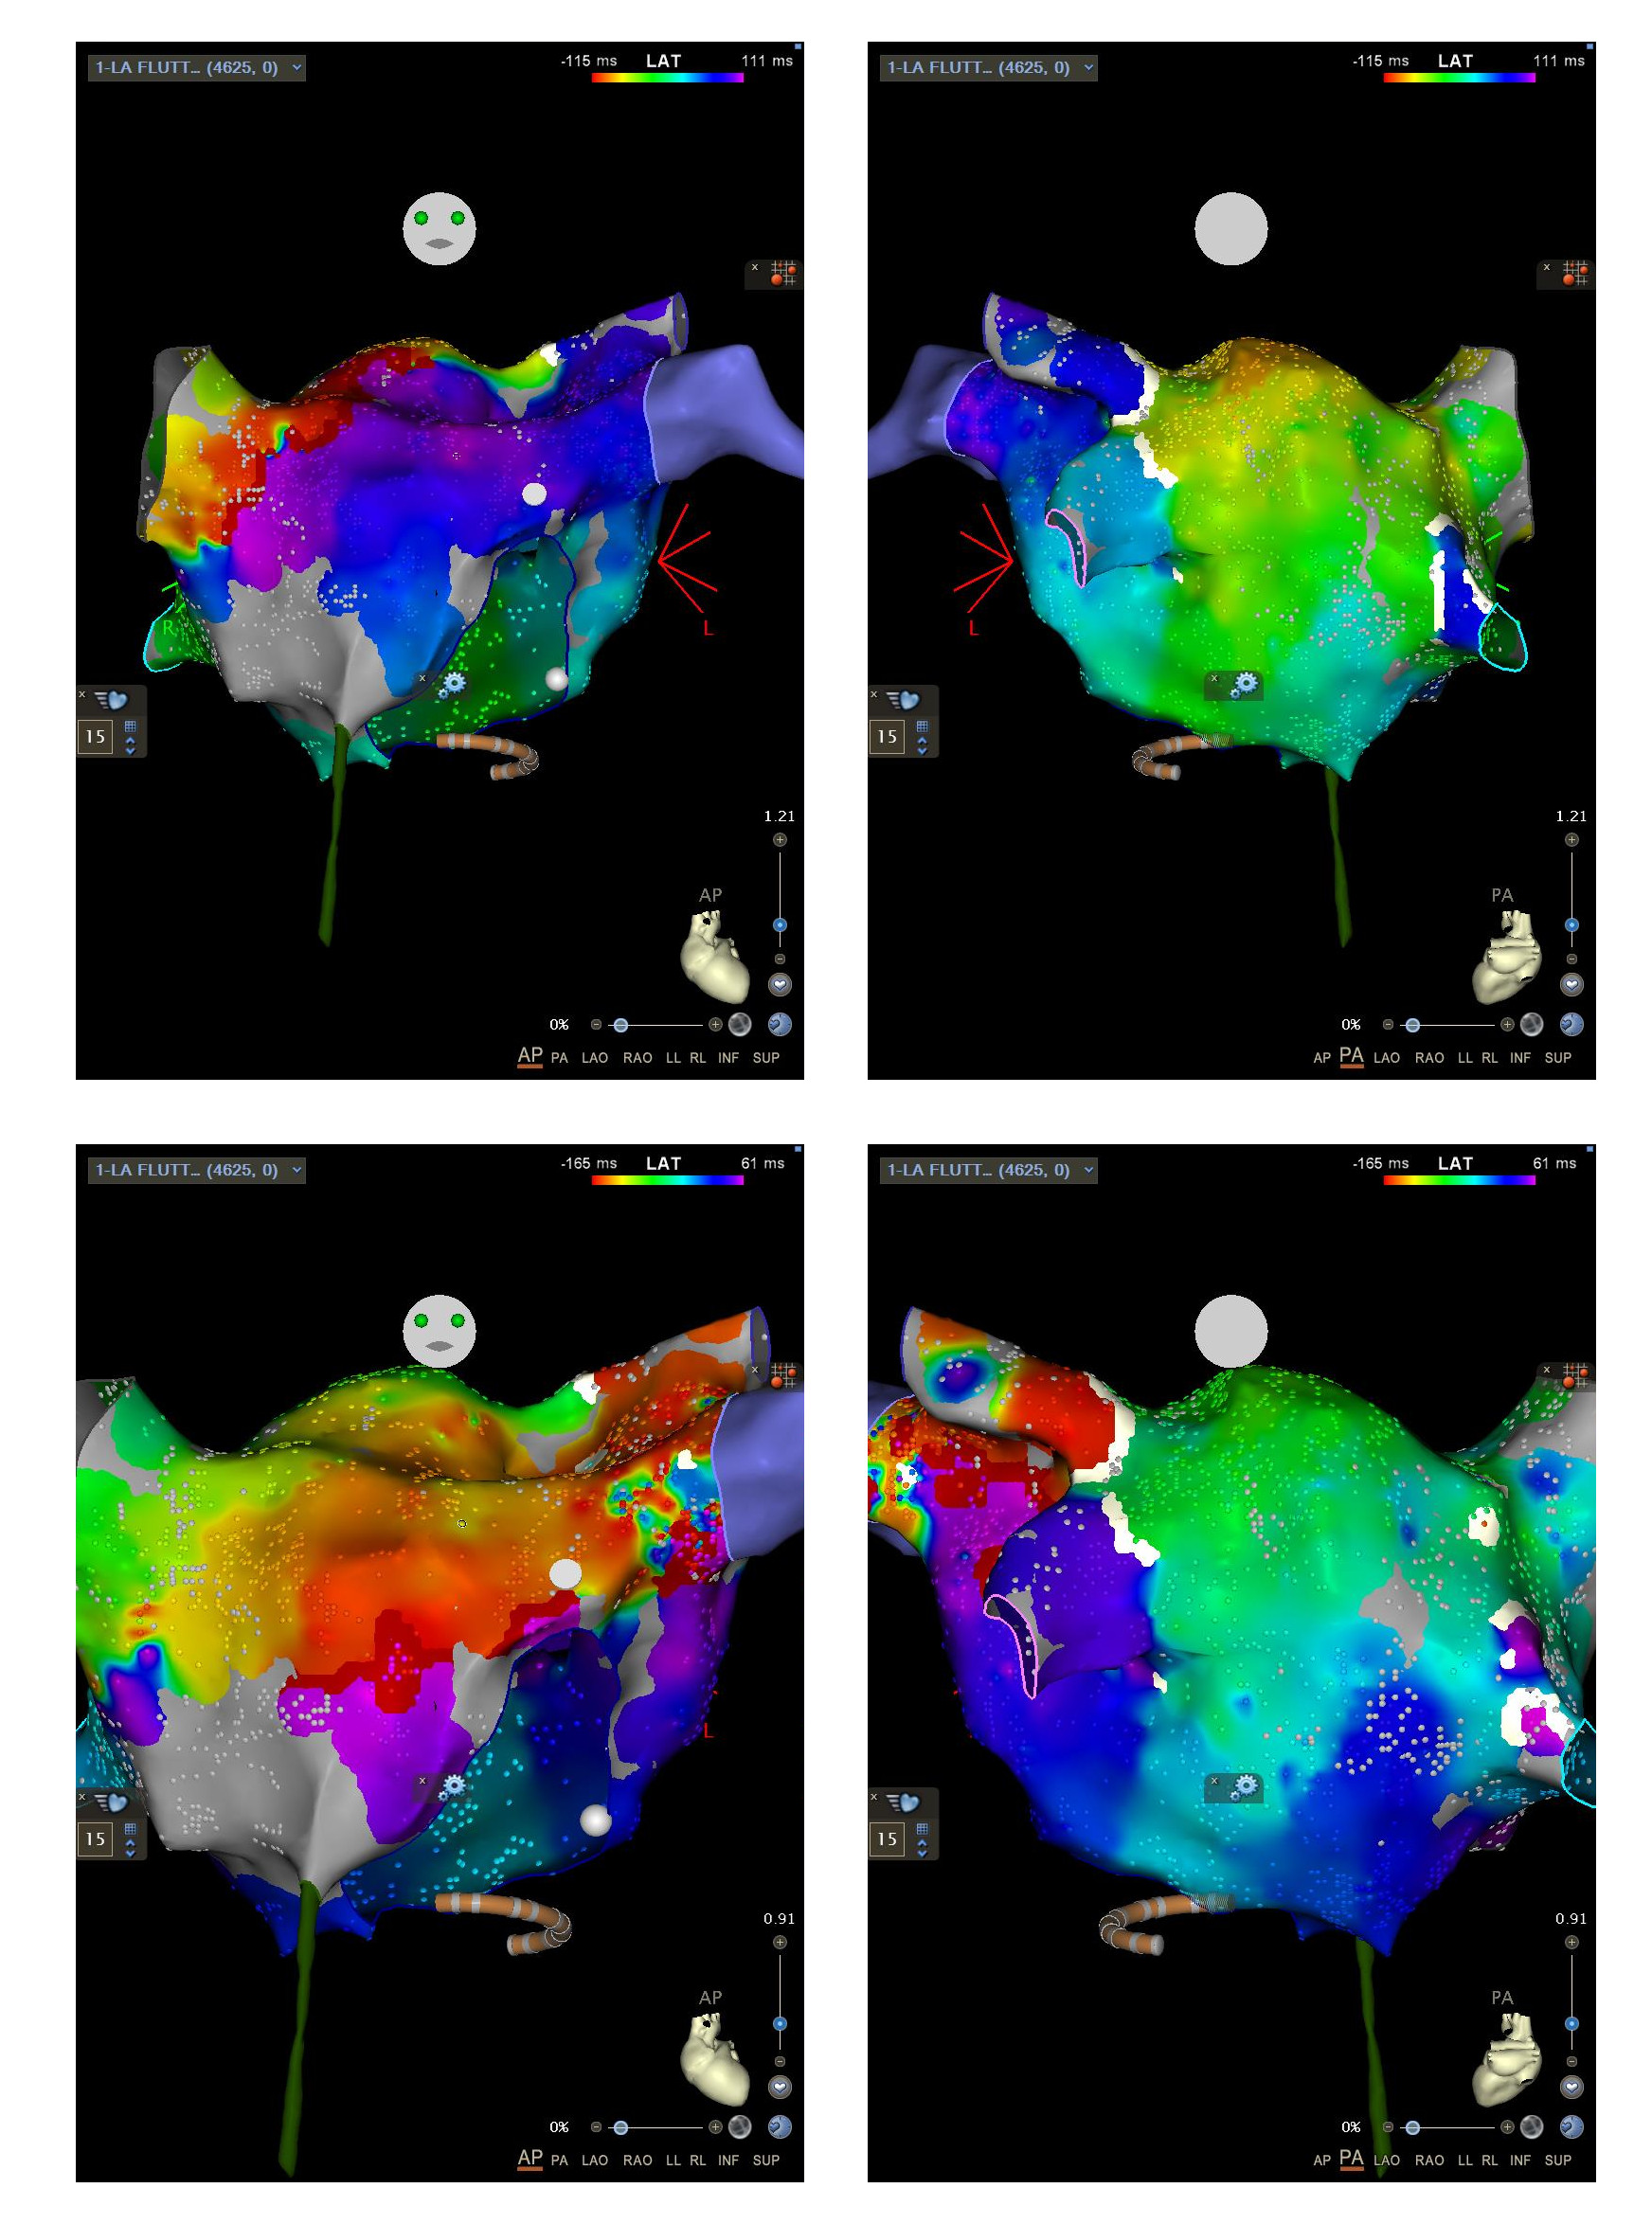

Setting the window of interest

Choosing a reference

Timing Reference

Window onset

schematic_window.png

window1.png

window2.png

komala_flutter_diff_windows.jpg

De Ponti method

deponti.gif

De Ponti R, Verlato R, Bertaglia E, Del Greco M, Fusco A, Bottoni N, Drago F, Sciarra L, Ometto R, Mantovan R, Salerno-Uriarte JA. Treatment of macro-re-entrant atrial tachycardia based on electroanatomic mapping: identification and ablation of the mid-diastolic isthmus. Europace. 2007 Jul;9(7):449-57. doi: 10.1093/europace/eum055. Epub 2007 May 3. PMID: 17478460.

No clear isoelectric segment

no_ponti1.png

Long P wave duration in relation to CL

no_ponti2.png

P end to P end

woi_p_wave.jpg

Mechulan A, Bun SS, Masse A, Peret A, Leong-Feng L, Pons F, Bouharaoua A, Dieuzaide P, Prévot S. An improved window of interest for electroanatomical mapping of atrial tachycardia. J Interv Card Electrophysiol. 2022 Jan;63(1):29-37. doi: 10.1007/s10840-021-00940-0. Epub 2021 Jan 27. PMID: 33506319; PMCID: PMC8755667.

Window length

• 80% of CL

• 90% of CL

• 100% of CL

Why not 100% ?

window_length.jpg